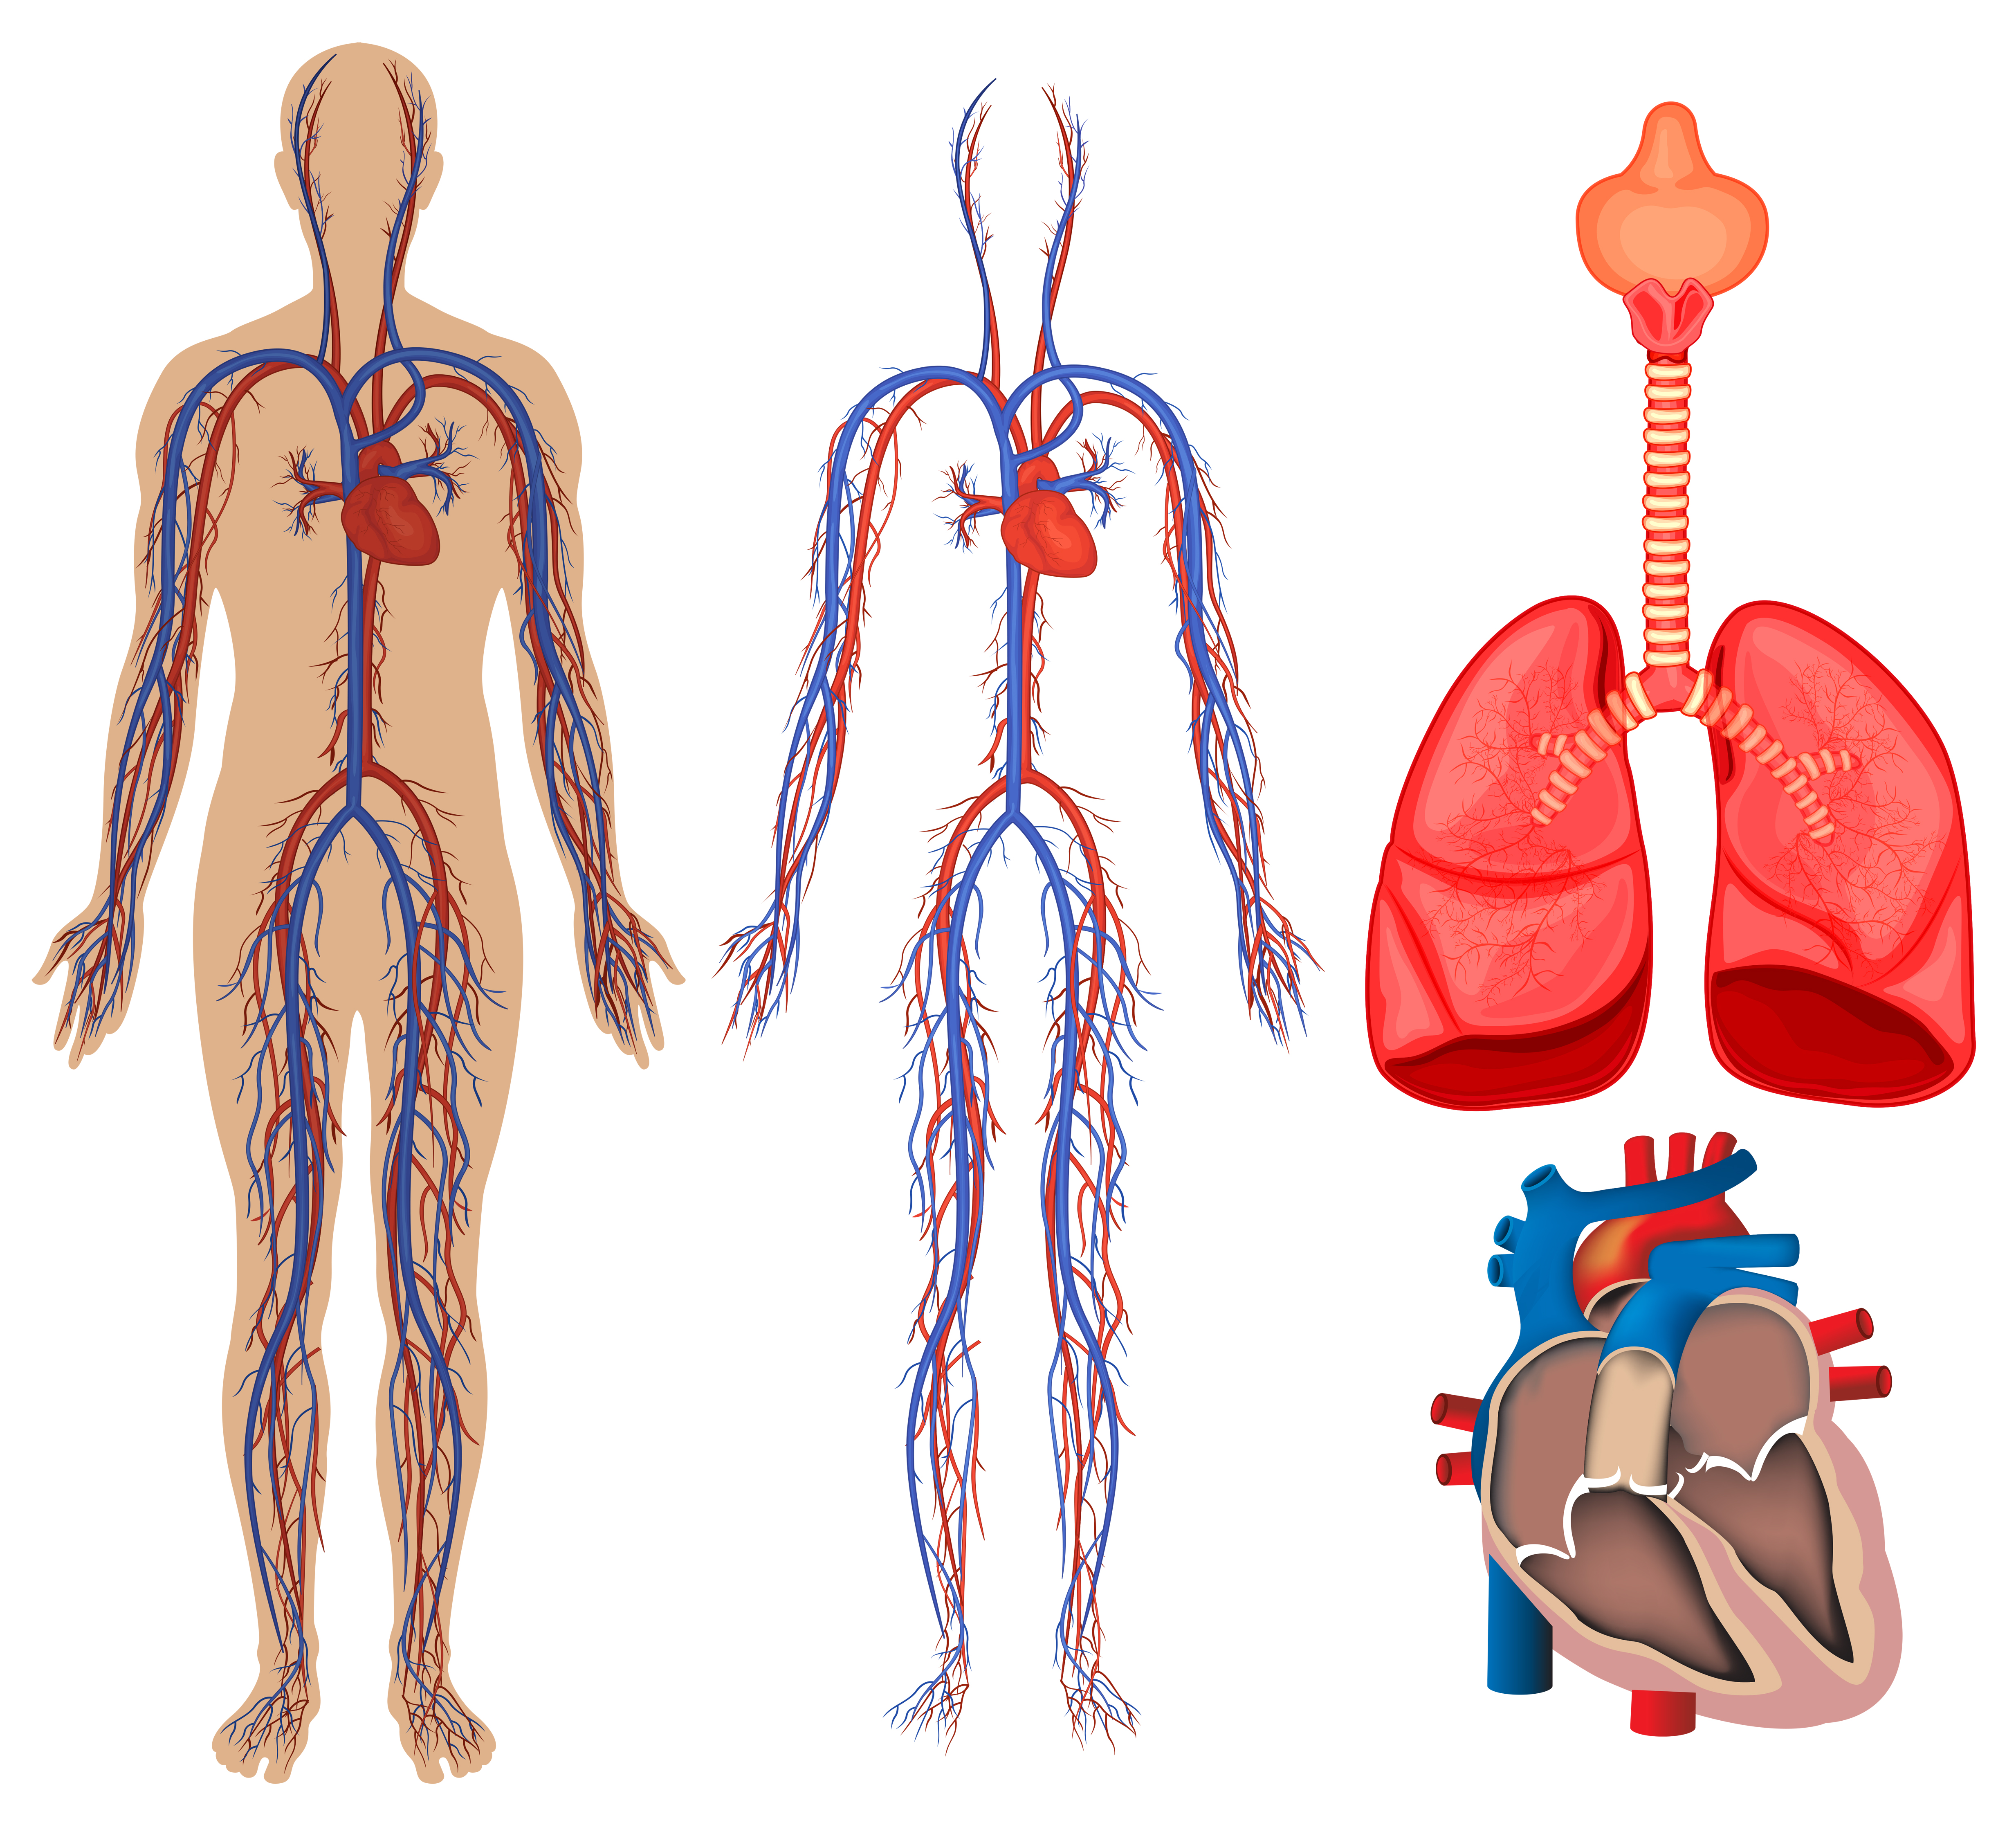

ระบบไหลเวียนโลหิต ทำหน้าที่อะไร และมีส่วนประกอบสำคัญอะไรบ้าง

ระบบไหลเวียนโลหิต ทำหน้าที่อะไร และมีส่วนประกอบสำคัญอะไรบ้าง 269,300+ ระบบหายใจ ระบบไหลเวียนโลหิต ภาพถ่ายสต็อก รูปภาพ และภาพปลอดค่า …

ระบบไหลเวียนเลือด: หัวใจ รูปภาพประกอบระบบไหลเวียนโลหิตของร่างกายที่วาดด้วยมือ PNG , ร่างกาย …

ระบบหมุนเวียนเลือด | Digestive System Quiz – Quizizz ระบบไหลเวียนโลหิตของมนุษย์ในระบบไหลเวียนโลหิต, สุขภาพ, ร่างกาย, หัวใจ …

ระบบไหลเวียนโลหิตของมนุษย์ในระบบไหลเวียนโลหิต, สุขภาพ, ร่างกาย, หัวใจ … LOWER SECONDARY SARASAS WITAED RANGSIT: ผลงานนักเรียน วิชา วิทยาศาสตร์ …

Heart Diagram กายวิภาคศาสตร์ร่างกายมนุษย์ระบบไหลเวียนโลหิตหัวใจ … ภาพประกอบระบบไหลเวียนโลหิตหัวใจเวกเตอร์ ภาพประกอบสต็อก – ดาวน์โหลดรูป …

ปอด ภาพประกอบสต็อก – ดาวน์โหลดรูปภาพตอนนี้ – iStock กายวิภาคของระบบไหลเวียนโลหิต ภาพประกอบสต็อก – ดาวน์โหลดรูปภาพตอนนี้ …

กายวิภาคของระบบไหลเวียนโลหิต ภาพประกอบสต็อก – ดาวน์โหลดรูปภาพตอนนี้ … ดาวน์โหลดฟรี | ระบบไหลเวียนเลือดการออกแบบ, แขน, ศิลปะ png | PNGEgg